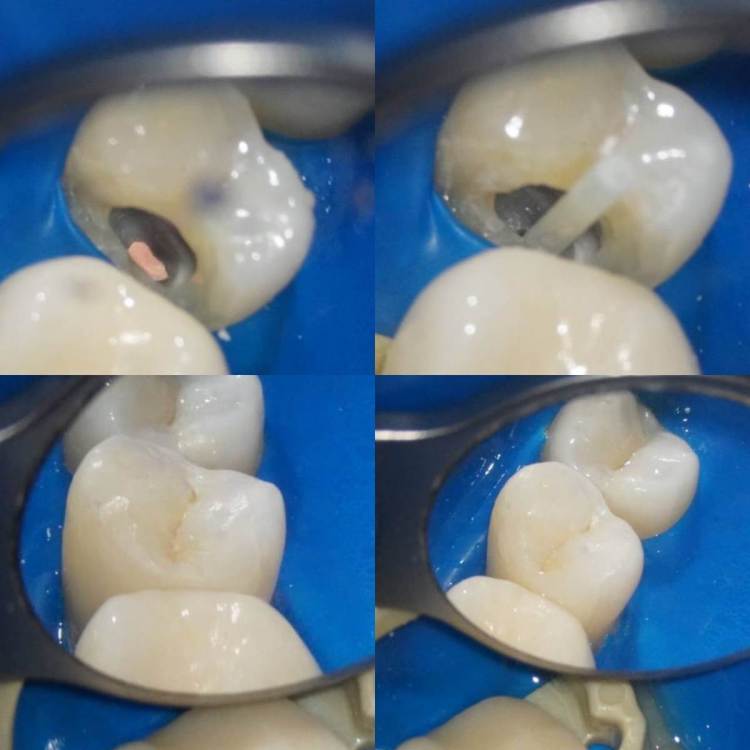

1586Doc Опубликовано 8 декабря, 2021 Автор Поделиться Опубликовано 8 декабря, 2021 Добавим эндо) Ретрит 46 зуб, 2 фрактуры в медиальных каналах. Один достаем, второй обходим )) 1 3 Ссылка на комментарий